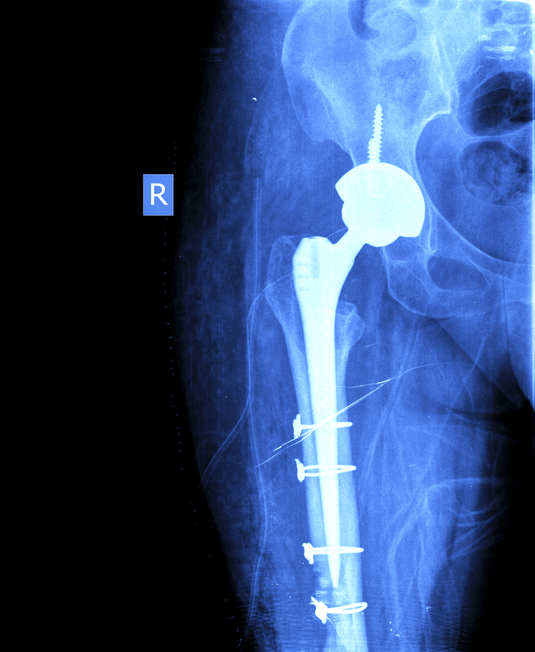

Certains gestes complémentaires sont parfois nécessaires pour enlever la prothèse et fixer correctement la suivante comme une ostéotomie fémorale d’exposition, l’apport de greffons osseux ou la pratique d’une ostéosynthèse par plaque, vis ou cerclage. ( voir radiographies ci-dessous).

Les différents types de descellement sont très variables et peuvent toucher le fémur et/ou le cotyle. C’est pourquoi les interventions de reprise sont toutes différentes, mais généralement la taille de la prothèse mise en place sera supérieure à votre ancienne prothèse.